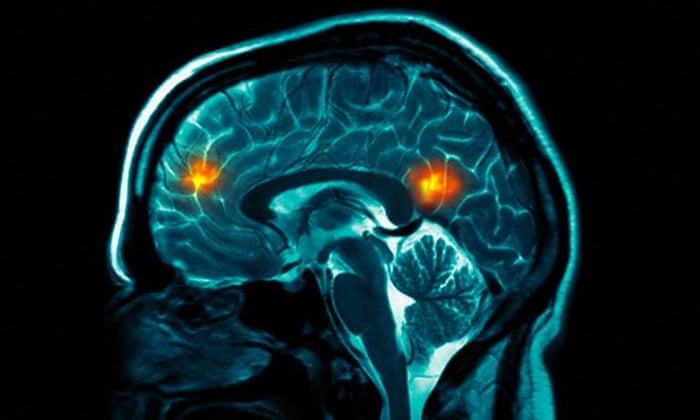

Mental health practitioners often try to sidestep this whole debate by claiming that most sensible professionals subscribe to a biopsychosocial model of mental distress. But unfortunately such a model nearly always ends up privileging the biological, despite the best intentions of many psychiatrists. As a society, we have a somewhat fetishistic relationship to bodies and brains, a moth-to-light-like attraction to shiny brain-imaging scans or a hint at a breakthrough in genetic research. Correlations between experiences and genetic phenotypes are conflated with evidence for molecular pathways that prove the existence of distinct disorders. Studies with only a few participants generate multiple headlines, and remain entrenched in the public imagination. At the same time, treatments that we know work fail to get funding due to the unconscious bias towards biological explanations.